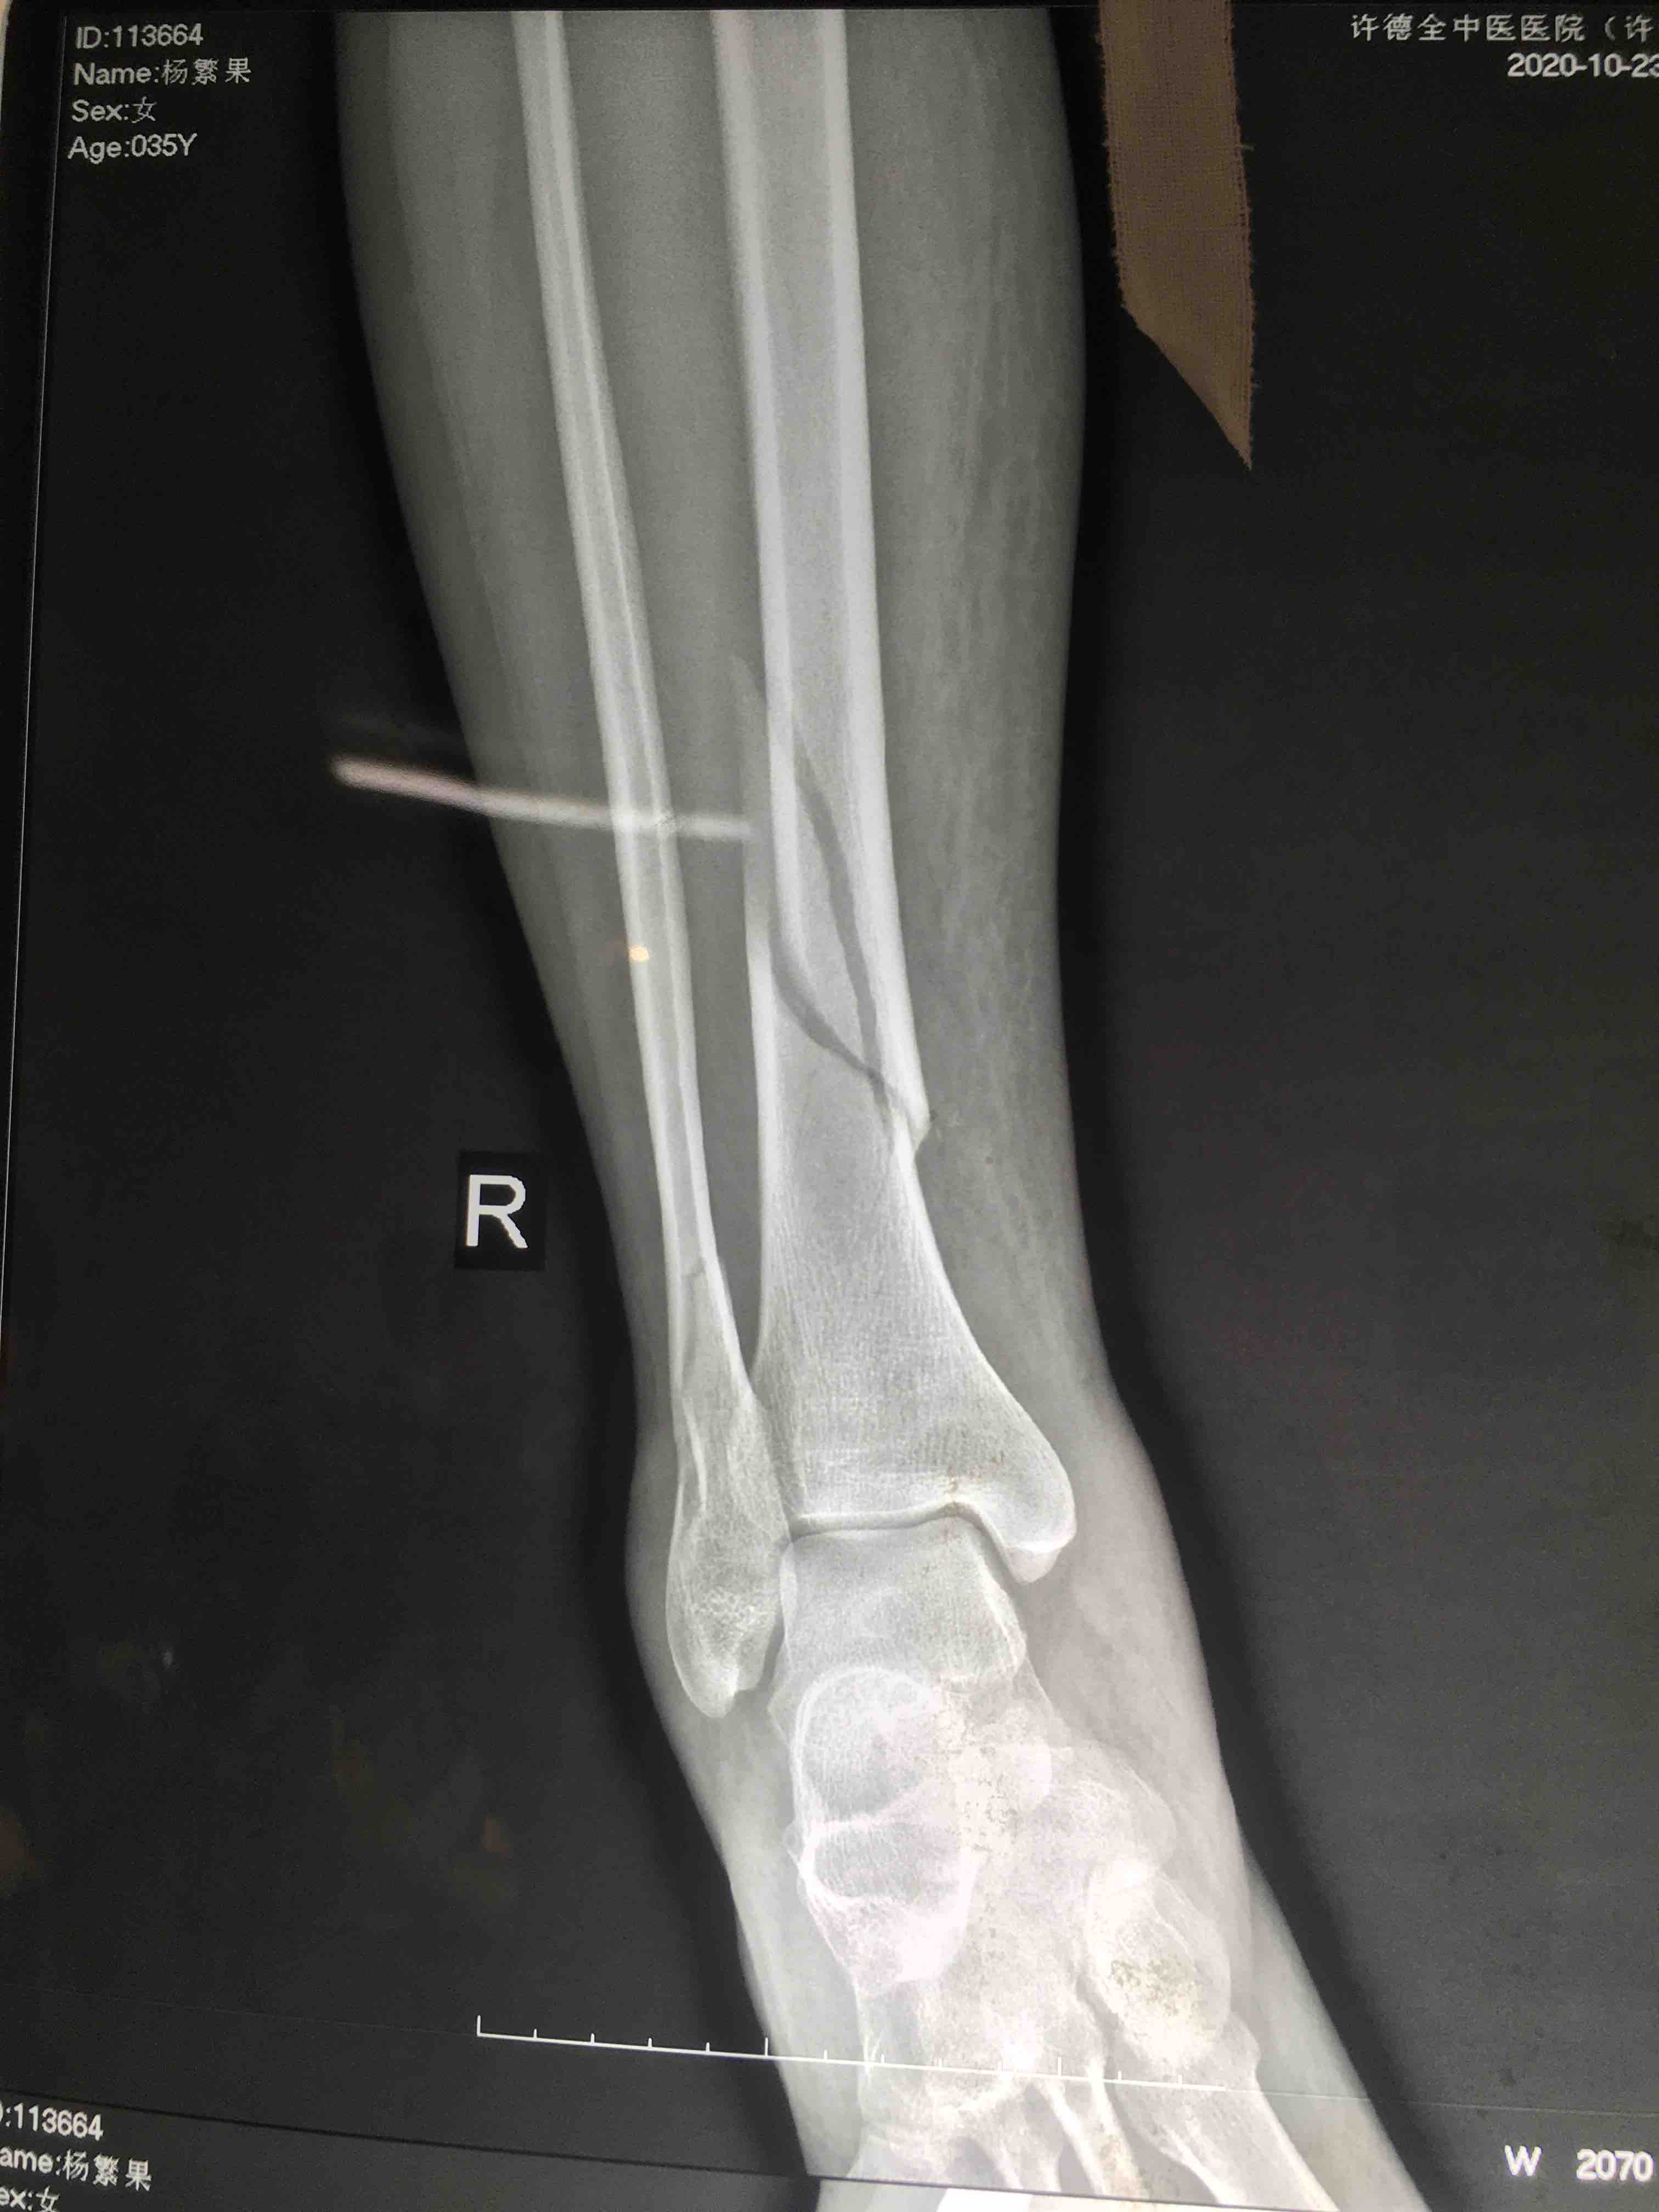

胫腓骨下段骨折(微创固定)

摔伤后右小腿肿痛,活动受限1小时入院。既往身体健康,无特殊不良嗜好。

生命体征平稳,心肺复未见明显异常。右小腿肿胀,局部皮色皮温正常,压痛及叩痛阳性,可及骨擦音,活动受限,末梢血运感觉正常。

在腰麻下行切复内固定术,术后抗炎,消肿对症治疗。